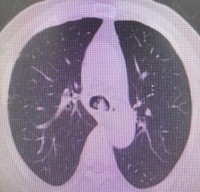

肺 部 C T (削瘤前)

于世寰主任介绍到,患者气管分叉处占位病变面积较大,已累及左、右主支气管,从肺CT影像上判断隆突区病变导致左主支气管狭窄约70-80%左右、右主支气管狭窄约50-60%左右,可操作空间十分有限,支气管镜介入治疗难度较大。隆突区占位病变已累及左右主支气管导致了呼吸困难已不适宜行外科手术治疗,必须通过支气管镜削瘤治疗来解除病人因气道梗阻导致的呼吸困难。支气管镜削瘤治疗与开胸外科手术相比,有痛苦小、创伤小、花费少、可重复性强、并发症少等优点。